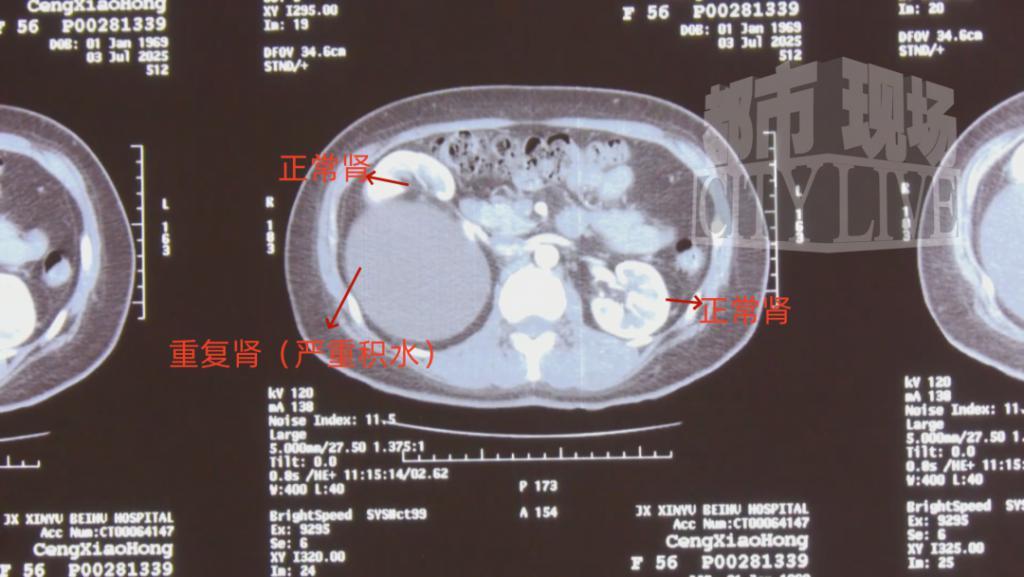

CT 检查显示,郑女士的的体内竟然有 " 三个肾 ",医学称之为重复肾。

新余市北湖医院泌尿外科 主任 袁剑:右边的肾有两个肾,这是一个肾,这下面重度积水的又是一个肾,左边是个正常的肾。这个积水很大,从上到下几十层应该有二十几公分长,这个大小应该是正常肾的三倍。